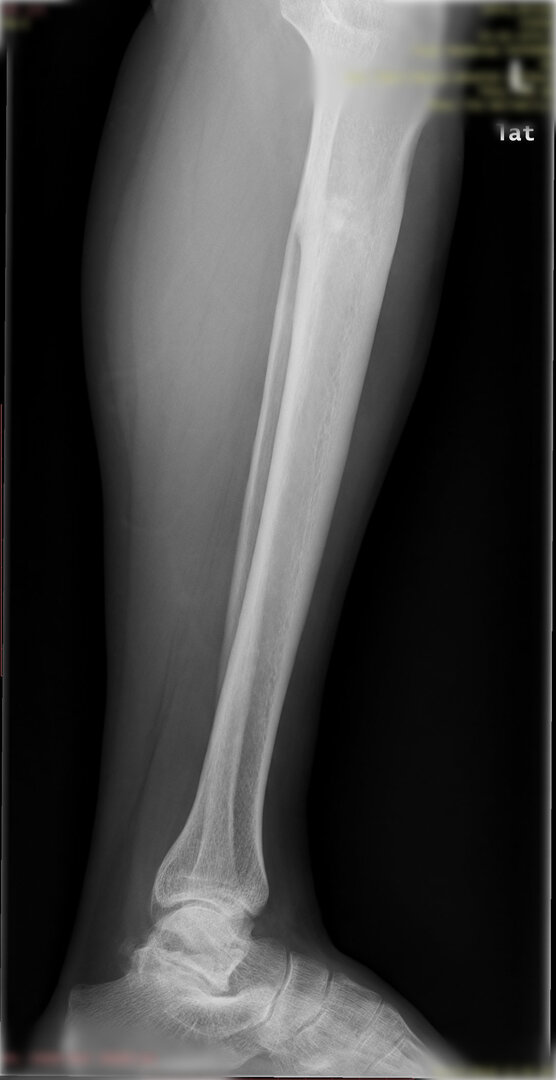

Diğer bir yöntem akut olarak düzeltme yöntemidir. Bu yöntemde kemiğe uygulanılan tespit yöntemi plak-vida kombinasyonu olabileceği gibi bir intramedüller çivi de olabilir.

Bu ameliyat öncesi bir deformite analizi yapılıp hangi kemikte, normalden ne kadar sapma olduğu tespit edilir. Daha sonra bu kemiğe yine ostetomi yapılarak bu anormal sapma düzeltilir.  Bu düzeltme plak-vida veya intramedüller çivi ile akut olarak düzeltilebileceği gibi bilgisayar destekli sirküler eksternal fiksatör ile tedrici olarak ta yapılabilir. Hangi yöntemin hangi hasta için uygun olacağına hasta özelinde karar veriyoruz, ne tür cerrahi tedavi olması gerektiğini danışabilirsiniz.